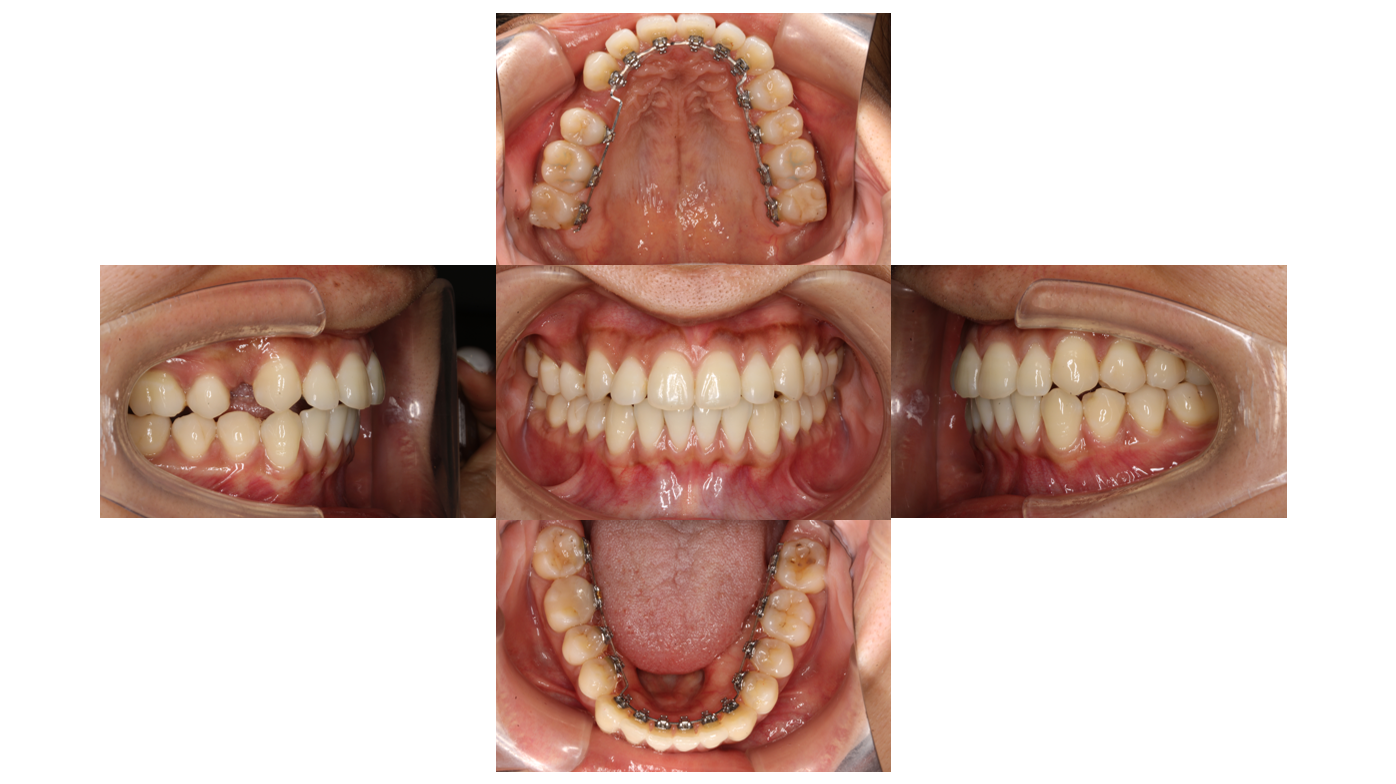

Before

初診